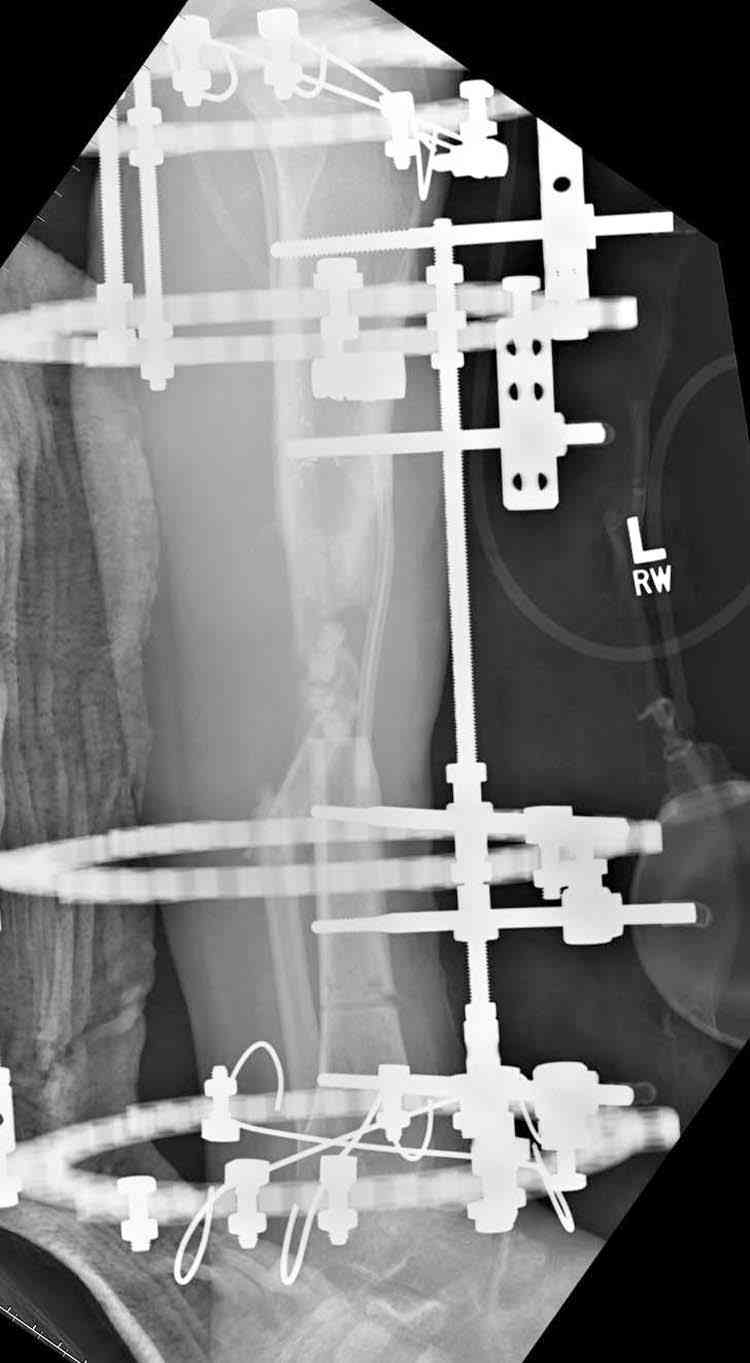

5. Ну и чтобы не быть голословным. Молодой человек подорвался на фугасе (Чечня, 2005 год). Свежие рентгенограммы:

Соответственно ожоги и дефект мягких тканей, переломы костей стопы и пр. Наложили аппарат

Илизарова (как придется), хирургически обработали и героически заживляли мягкие ткани с многочисленными кожными пластиками. В итоге через полгода я принял его вот таким:

Реализовал описанную выше методику, и в итоге вот что получилось. Высылаю лишь прямые проекции,

в боковых тоже всё в тему.

Очень пригодились карбоновые кольца (Джолдас -огромное спасибо, я твой должник!!!), поскольку остеопороз дистального отломка был просто невероятный. На цифровом рентгене с трудом угадывались контуры.

Рентген в процессе перемещения - внизу карбоновые кольца, тракция фрагмента спицами с упором.

внешний вид в аппарате - не завершающем этапе, сначала стопа тоже была фиксирована в аппарате.

Сейчас аппарат сняли, но случай ещё не завершенный.

Признаюсь честно, не совсем уверен в прочности консолидации на стыке косточек. Кроме того, укорочение в районе 6 см. Сейчас реабилитация - ходит опираясь на ногу с одним костылем.

Продолжение, видимо, будет... Возможно, будем удлинять.